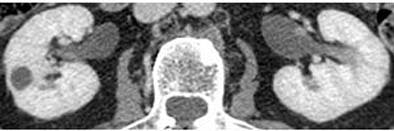

| Parenchymal phase (above), excretory phase (below), and MIP images (bottom) from a patient with a high-grade superficial recurrence of transitional cell carcinoma in the left renal pelvis. Images courtesy of Dr. Theresa Koppie. |